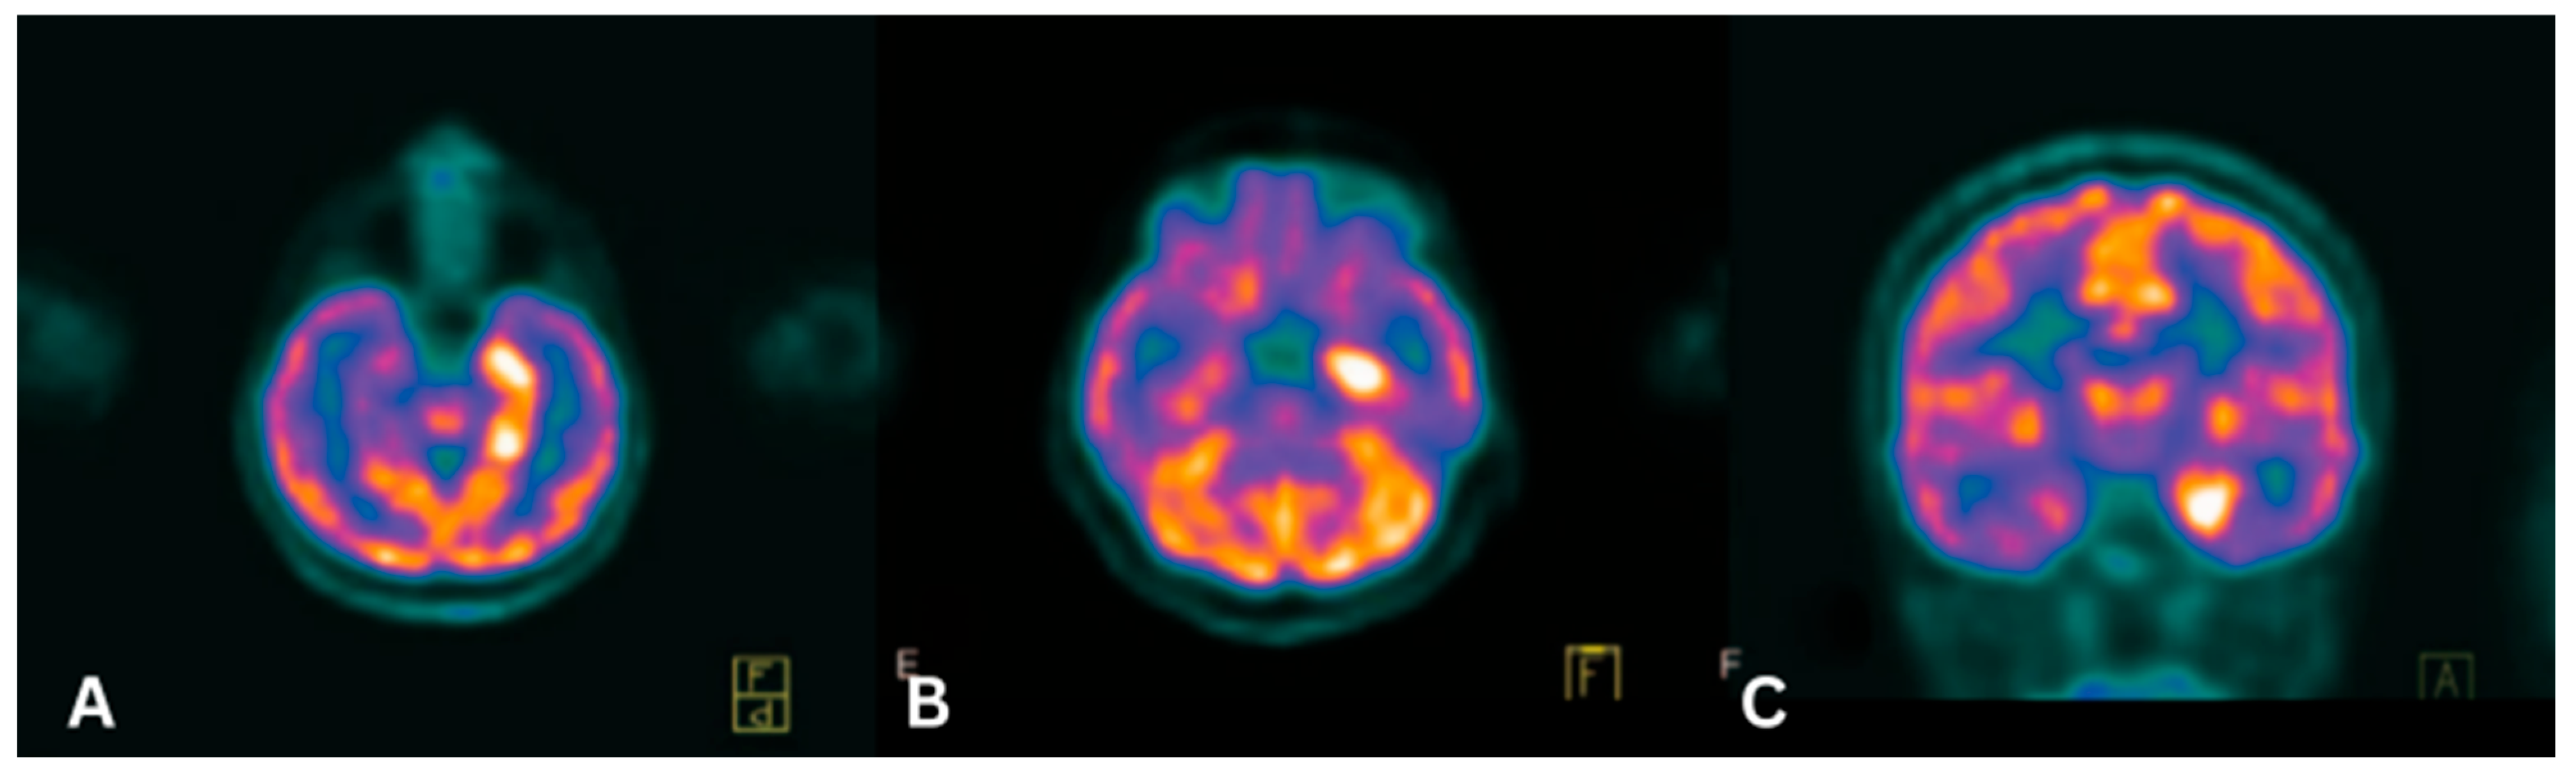

- Bordonne, M.; Chawki, M.B.; Doyen, M.; Kas, A.; Guedj, E.; Tyvaert, L.; Verger, A. Brain 18F-FDG PET for the Diagnosis of Autoimmune Encephalitis: A Systematic Review and a Meta-Analysis. Eur. J. Nucl. Med. Mol. Imaging 2021, 48, 3847–3858. [Google Scholar] [CrossRef] [PubMed]

- Deuschl, C.; Rüber, T.; Ernst, L.; Fendler, W.P.; Kirchner, J.; Mönninghoff, C.; Herrmann, K.; Quesada, C.M.; Forsting, M.; Elger, C.E.; et al. 18F-FDG-PET/MRI in the Diagnostic Work-up of Limbic Encephalitis. PLoS ONE 2020, 15, e0227906. [Google Scholar] [CrossRef]

- Scheid, R.; Lincke, T.; Voltz, R.; von Cramon, D.Y.; Sabri, O. Serial 18F-Fluoro-2-Deoxy-D-Glucose Positron Emission Tomography and Magnetic Resonance Imaging of Paraneoplastic Limbic Encephalitis. Arch. Neurol. 2004, 61, 1785–1789. [Google Scholar] [CrossRef] [PubMed]

- Abdulaziz, A.T.A.; Yu, X.Q.; Zhang, L.; Jiang, X.Y.; Zhou, D.; Li, J.M. Paraneoplastic Cerebellar Degeneration Associated with Cerebellar Hypermetabolism. Med. Baltim. 2018, 97, e10717. [Google Scholar] [CrossRef]

- Massa, F.; Filippi, L.; Benedetti, L.; Morbelli, S.; Nobili, F. FDG PET Unveils the Course of Paraneoplastic Cerebellar Degeneration: A Semiquantitative Analysis. Clin. Nucl. Med. 2021, 46, e327–e328. [Google Scholar] [CrossRef]

- Masangkay, N.; Basu, S.; Moghbel, M.; Kwee, T.; Alavi, A. Brain 18F-FDG-PET Characteristics in Patients with Paraneoplastic Neurological Syndrome and Its Correlation with Clinical and MRI Findings. Nucl. Med. Commun. 2014, 35, 1038–1046. [Google Scholar] [CrossRef]